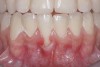

Fig 2. Pre-treatment clinical view of a 28-year-old patient with Miller Class I recession of the lower left central incisor treated with conservative SPT.

Figure 2